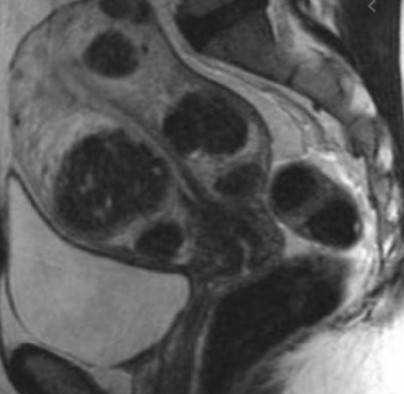

- УЗИ матки. Миоматозные узлы имеют вид округлых гетерогенных образований с четкими ровными контурами. При преобладании в составе низкодифференцированных гладкомышечных клеток неоплазия является гипоэхогенной, о наличии большого количества соединительнотканных волокон свидетельствует гиперэхогенность. Метод позволяет четко определить размеры опухоли, количество узлов и их расположение.

- МРТ малого таза. Отражает точную топографию, размер и количество миоматозных узлов. Часто шеечная опухоль сочетается с миомами тела матки. Данные исследования используются при выборе тактики лечения.

Признаки миомы на МРТ

Диагностировать миому на МРТ не составляет особого труда. Врачи на томографических изображениях видят её в виде четко очерченного образования округлой формы. На магнитно-резонансных снимка определяется псевдокапсула миомы в виде тонкого ободка, гиперинтенсивного по Т2. По МР картине специалист может говорить о характере миомы, является ли она кистозной или миксоидной, лейомиомой или липолейомиомой. В зависимости от неоднородности миомы будут видны сопутствующие процессы - кровоизлияние, некроз, обызвествление.

При магнитно-резонансной томографии получают множественные снимки анатомической зоны во фронтальной, сагиттальной и аксиальной плоскостях. Врач имеет возможность изучить каждый участок органа, выявить малейшие отклонения от нормы. Миоматозные узлы обычно выглядят на МР-сканах как округлые гипоинтенсивные образования разных размеров. Смена режимов позволяет выявить псевдокапсулу, оценить характер кровоснабжения опухолей.

Если на МРТ нашли миомные узлы, рентгенолог описывает локализацию, размеры, количество, тип образований. Врач может выявить кровоизлияния, очаги обызвествления и некроза. Сведения о новообразованиях специалист фиксирует в заключении. Результаты МРТ изучает клиницист. На основании выводов рентгенолога, гинеколог ставит окончательный диагноз и выбирает способ лечения.